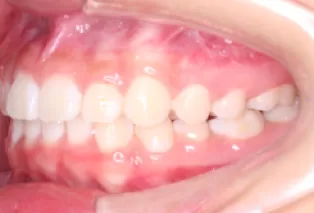

Photos intra-orales